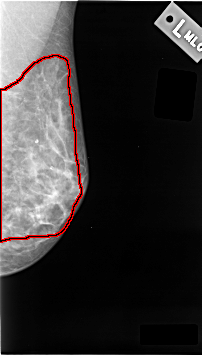

C_0039_1.LEFT_MLO

LEFT_MLO LINES 4648 PIXELS_PER_LINE 2616 BITS_PER_PIXEL 12 RESOLUTION 50 OVERLAY

FILE: C_0039_1.LEFT_MLO.OVERLAY

TOTAL_ABNORMALITIES 1

ABNORMALITY 1

LESION_TYPE CALCIFICATION TYPE AMORPHOUS DISTRIBUTION DIFFUSELY_SCATTERED

ASSESSMENT 3

SUBTLETY 4

PATHOLOGY MALIGNANT

TOTAL_OUTLINES 1

BOUNDARY